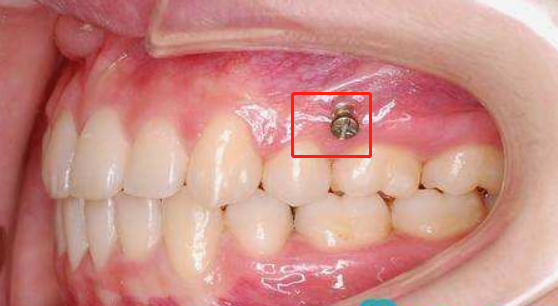

骨釘,顧名思義,是一種外形十分像釘子的種植釘,是放置在牙骨上方一個迷你的"釘子"。

它體積的小,好植入,近年來,逐漸成為正畸科常用的正畸輔助工具。

疼痛感因人而異,如果術(shù)后有疼痛感可伴隨止痛藥來緩解。一般情況下,一天就可以緩解脹痛感。由于骨釘是一個略微突出,由于角度或者黏膜厚度的問題,容易產(chǎn)生摩擦的狀況,如果出現(xiàn)這種狀況,只要及時告知醫(yī)生,讓醫(yī)生做適當(dāng)調(diào)整來減輕不適。

植入骨釘意味著正畸正式開始,維護好骨釘,也是牙齒矯正中一項重要的后期工作,植入骨釘后,就意味著,為細(xì)菌創(chuàng)造了一個藏匿的地點,做好口腔清潔是維護好骨釘,保護好牙齒健康重要一個步驟